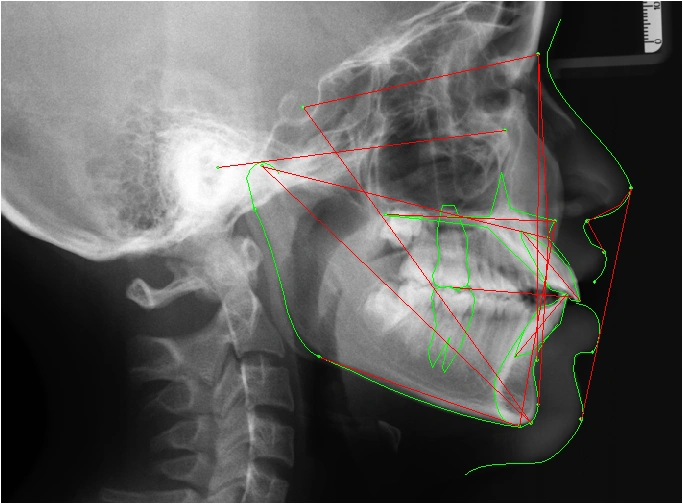

- Chụp phim 3D, chụp ảnh.

Để chẩn đoán và lập kế hoạch điều trị chỉnh nha tốt nhất. Hệ thống máy chụp phim panorama và cefalo kỹ thuật số, tích hợp phần mềm bản quyền Align Pro. Trang bị này cho phép bác sĩ chỉnh nha chẩn đoán, lập kế hoạch và điều trị giả định.